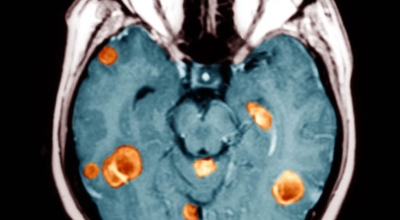

뇌종양 초기증상 여섯 번째는 교모세포종의 문제입니다. 가장 흔한 뇌종양은 수막종이며 종양의 크기나 위치에 따라 수술이 필요하지 않을 수 있지만 청각 신경초종은 이명을 나타나게 할 수 있고 심한 경우 안면 마비, 경련 및 통증을 유발할 수 있지만 뇌종양은 생존을 좌우하게되는 교모세포종 문제가 뒤늦게 생기는 것으로 주의가 필요한 이유입니다.

악성 뇌종양은 뇌암이라고도 하고, 성장 속도가 빠르며 주위 조직으로의 침투 역량이 강해요. 이에 따라 정상 뇌 조직으로 침윤되고 정상 뇌 조직과의 경계가 불분명해서 치료가 어려운 편이예요. 악성 뇌종양은 주변의 정상 뇌 조직을 빠른 속도로 파괴해요.